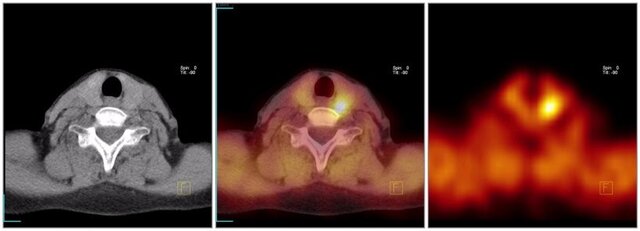

• PET y SPECT

PET y SPECT

Cámara gamma, tomografía por emisión de positrones (PET) y SPECT.

Medicina nuclear

La Medicina Nuclear inicia su desarrollo como especialidad a finales de los años 40, momento en el que se decide utilizar la energía nuclear con fines médicos. En 1946 se construye el primer reactor productor de radionúclidos.